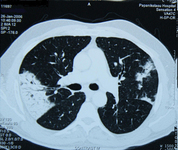

Chest CT scan of a patient with amiodarone pulmonary toxicity, showing asymmetric opacities with a peripheral distribution

From the collection of Athanasia Pataka, MD